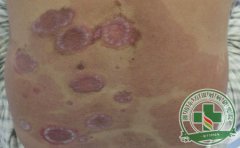

银屑病是一种危害很大的皮肤疾病,也是世界上三大皮肤病之一,可见银屑病的危害有多么强烈,然而相对于及时治疗银屑病来时,平常的银屑病护理也是很关键的。[详细]